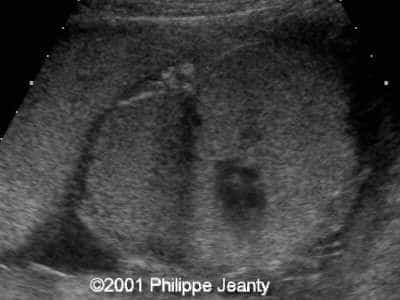

This 2nd trimester fetus has the following images (actually, these images remained unchanged for several weeks)

The findings are:

• very enlarged lungs on both sides

• inversion of the diaphragm that is convex towards the abdomen

• small compressed heart

• ascites but no generalized hydrops (no skin thickening for instance)

A much more common diagnosis for a bilateral echogenic lung associated with microcardia and ascites (Budd-Chiari phenomenon) is Larynx, atresia or as reported by several the CHAOS syndrome which stands for Congenital High Airway Obstruction Syndrome (which is typically laryngeal or tracheal atresia). This is the diagnosis that was indeed suspected in this fetus.